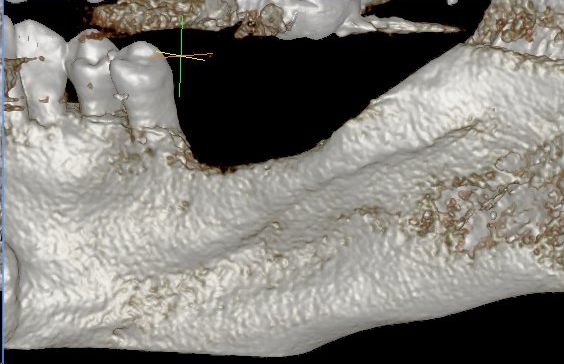

13/28 - Model of the augmented ridge before implantation computed from CBCT-recordings - lingual viewThree-dimensional augmentation with maxgraft® cortico - Dr. R. Würdinger